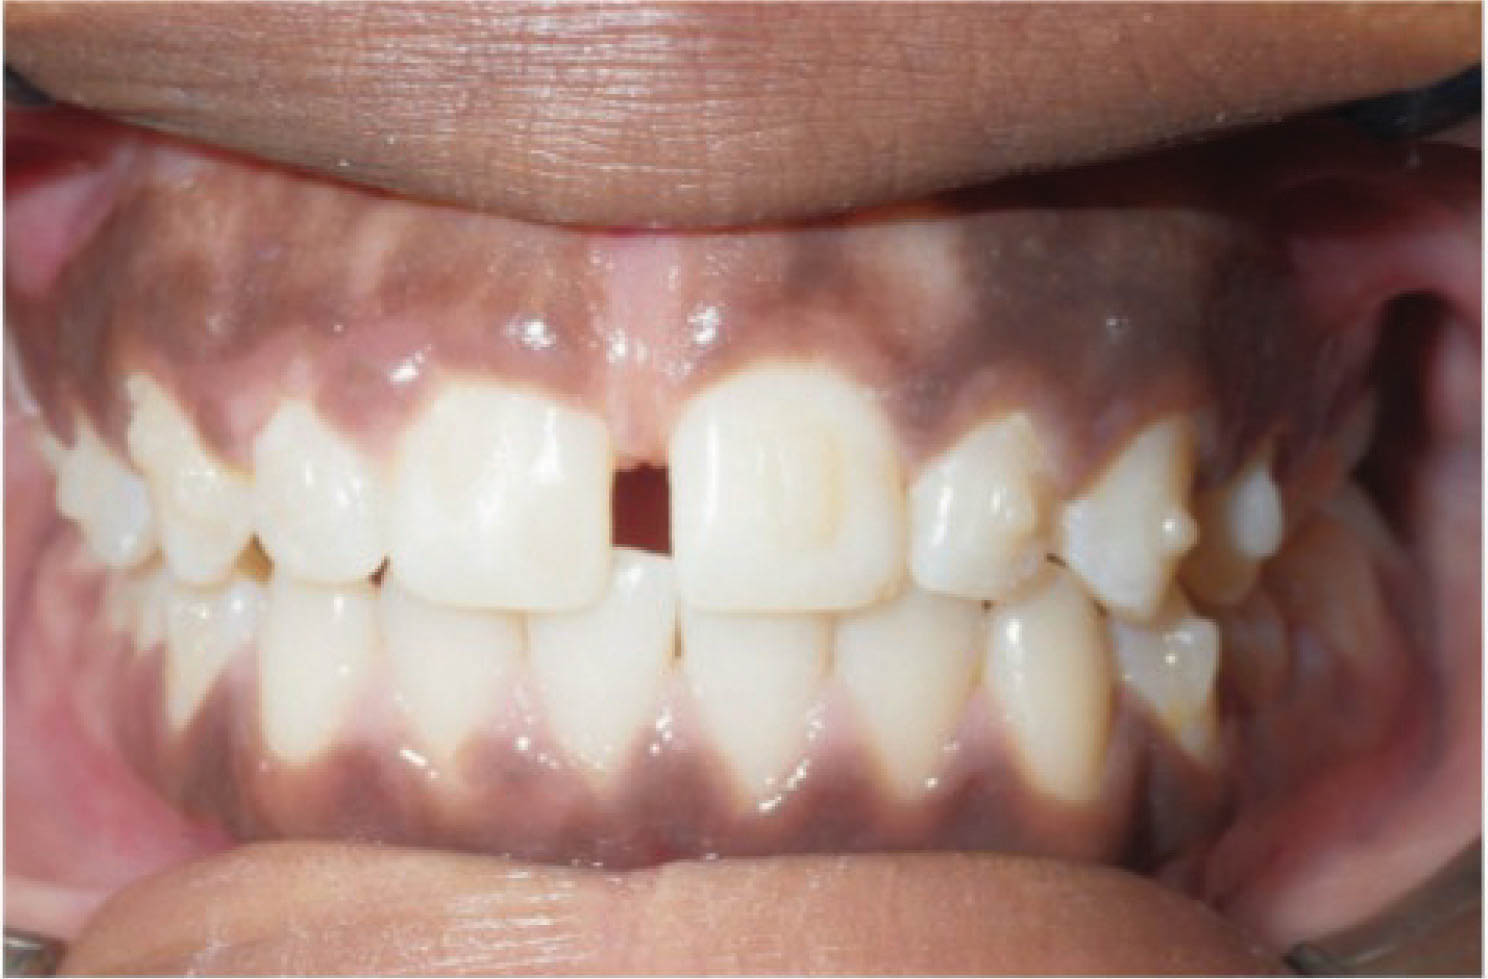

در بیماری که در شکل 38-6 مشاهده میکنید، یعنی بیماری که سانترالهای بالا او از هم به صورت تیپینگ دور شدهاند، درمان با الاینر خیلی عالی میشود، و تصویر آخر نرم افزار به نتیجه درمان خیلی شبیه میشود (شکل 39-6 و 40-6).

شکل 38-6